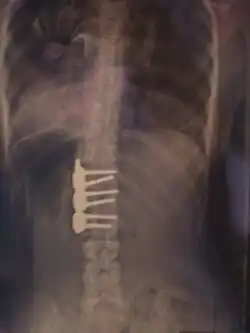

Хирургическое лечение

При неуспехе бескровного консервативного лечения из-за нарушения предписанного режима ношения корсета, плохого качества изготовленного корсета или отказе от него рассматривается операция по установке металлических конструкций и аутотрансплантантов (небольших фрагментов кости таза пациента, превращённых в костную крошку) фиксирующих между собой тела позвонков, называемая «спондилодез» или «fusion»-закрепление(слияние, заваривание).

При оперативном лечении искривлённая часть позвоночника выпрямляется до определённого возможного угла при помощи металлических стержней и шурупов (т. н. транспедикулярных винтов), что ведёт к полному обездвиживанию этих отделов позвоночника. Операция при сколиозе подходит прежде всего для сильных искривлений, которые больше не могут лечиться другими методами. Оперативная фиксация может предотвратить дальнейшую прогрессию и ухудшение состояния.

Для коррекции в определённых сегментах удаляют диски и сбоку в корригируемые позвонки вводят шурупы. Их соединяют стержнем и после коррекции прикрепляют к нему. На место вынутых дисков вводят подготовленный костный материал. При современной методике операции для лучшей стабильности применяют два стержня, если это позволяет состояние позвоночника.